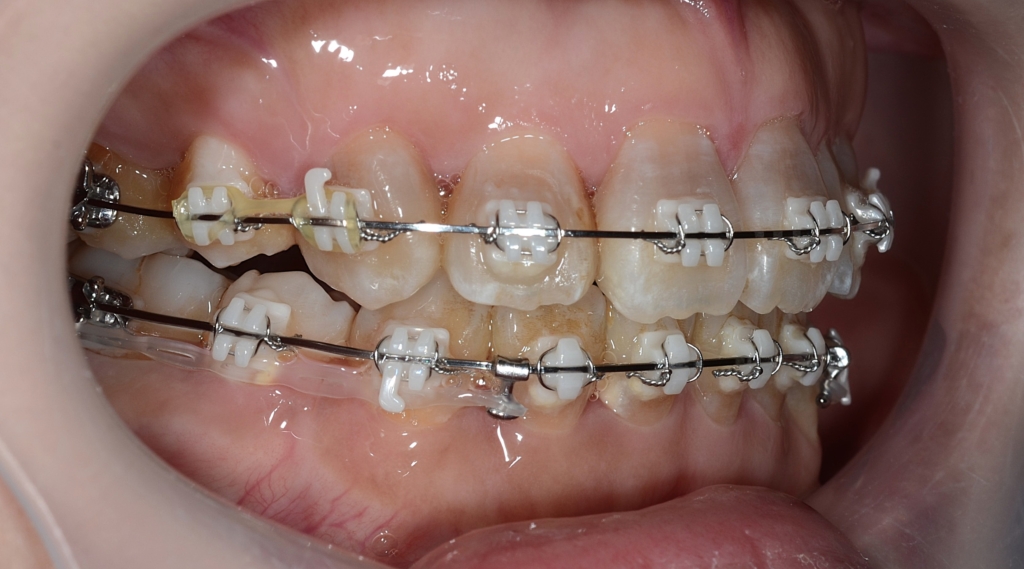

最終的に仕上げの微調整をして・・・

【After】

「もう十分です」という患者さんの声に許してもらいました

【保定】 上下ともフィックスタイプ&クリアリテーナー

【治療期間】 2年3カ月間

【治療費用】 81万6千円